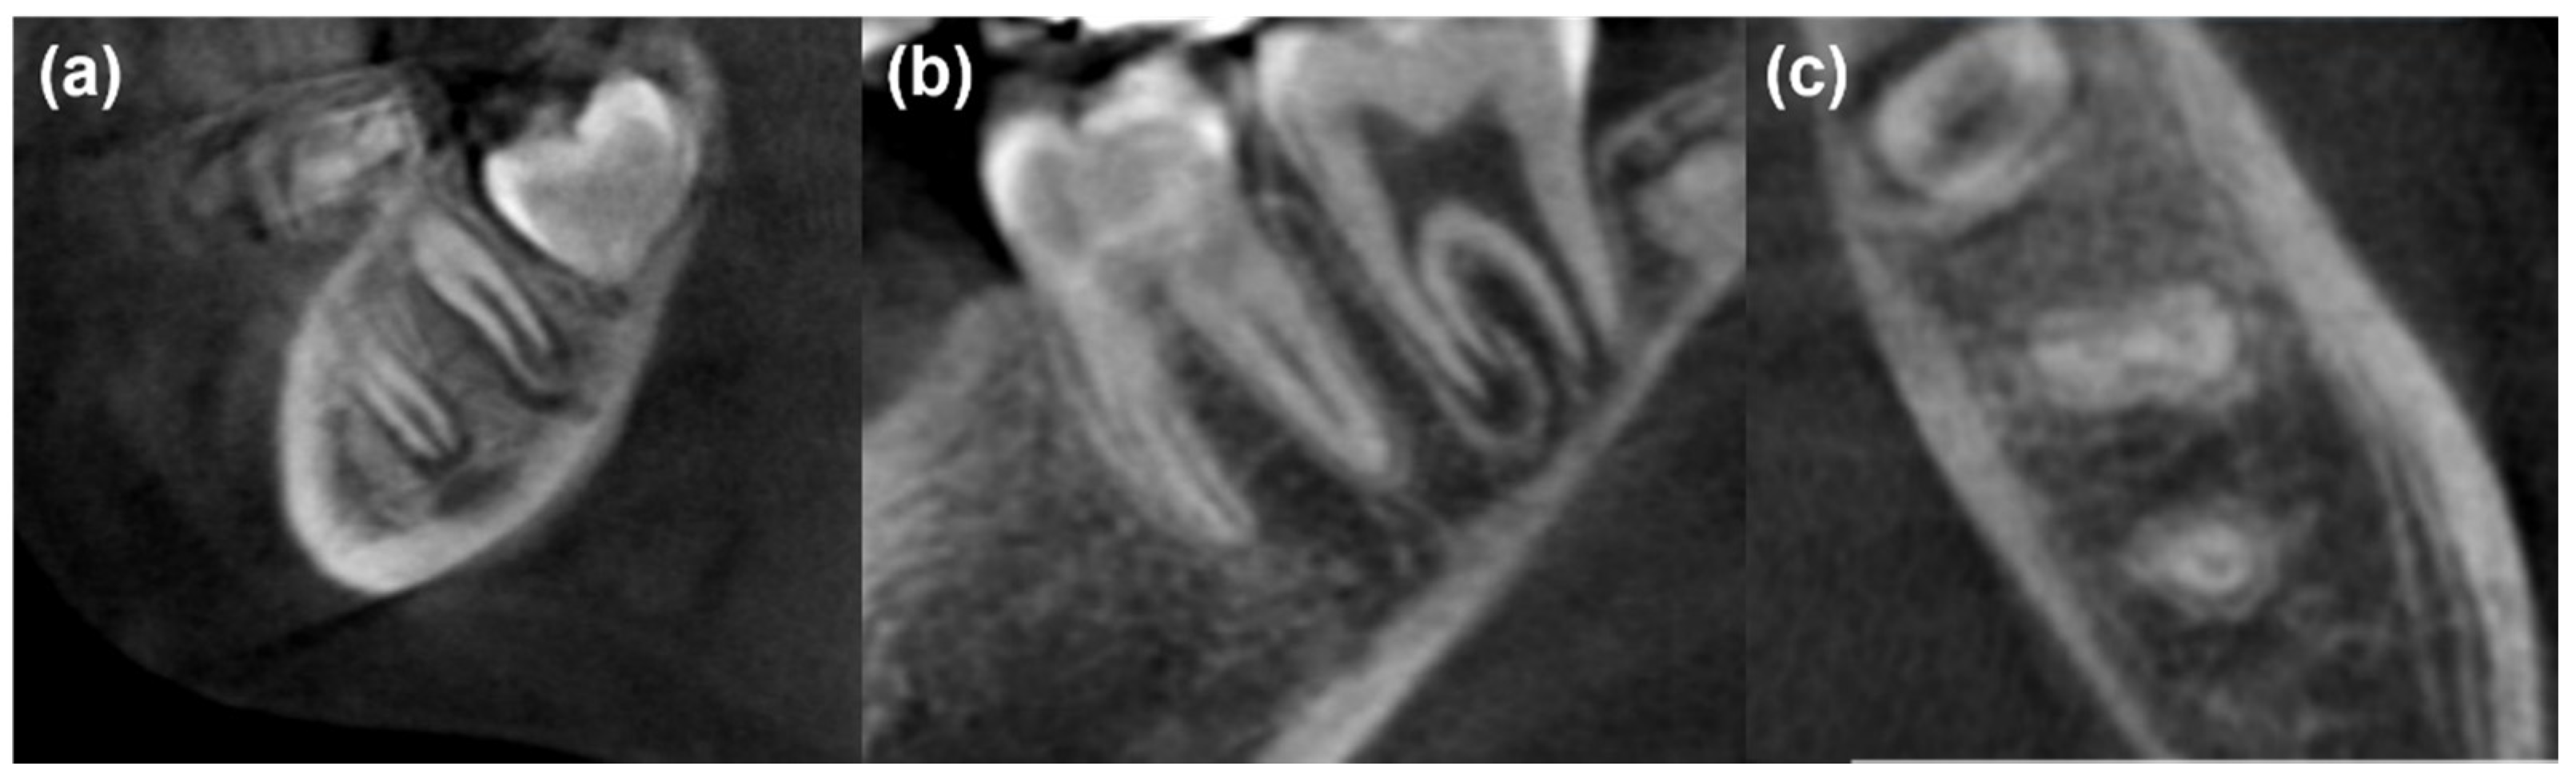

| Criteria/Group | MM-MTA (G1) | Nano-Hydroxyapatite (G2) | PRF (G3) | Statistical Analysis |

|---|---|---|---|---|

| Age (years) | 8.6 ± 2.0 | 8.8 ± 1.8 | 8.8 ± 2.1 | p = 0.911 |

| Sex females (%) | 11 (55) | 10 (50) | 9 (45) | p = 0.819 |

| Apical closure complete (6 months) (%) | 5 (25) | 3 (15) | 4 (19.04) | p = 0.726 |

| Apical closure complete (12 months) (%) | 10 (50) | 11 (55) | 12 (60) | p = 0.817 |

| Canal obliteration (6 months) (%) | 3 (15) | 4 (20) | 0 (0) | p = 0.111 |

| Canal obliteration (12 months) (%) | 7 (35) | 9 (45) | 1 (5) | p = 0.014 * |